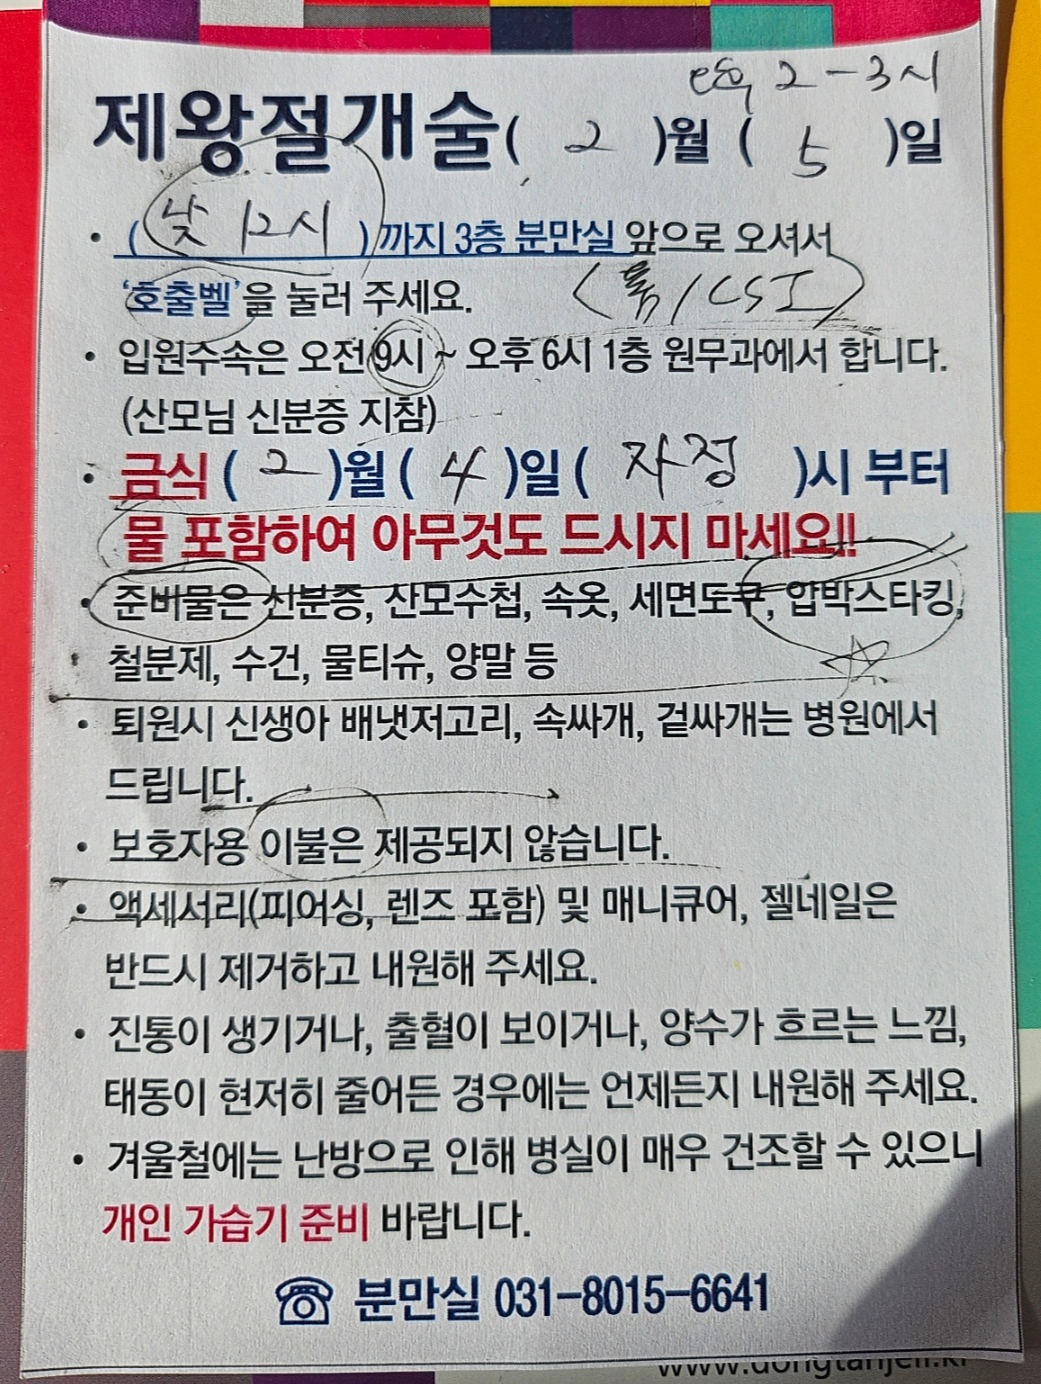

정기검진 초음파 진료 및 출산 안내

수술 일정, 입원 수속 안내 및 수술시 약제 선택 하기.

입원 수속 안내

수술 전날 오후 2시 동탄제일병원 홈페이지에서 입원 수속 대기 번호표 뽑기 하면 문자로 순번이 날아옴.

수술 당일 남편 홀로 아침 9시 방문 후 입원 수속 진행 후 집에서 대기하다 낮 12시 제왕 하러 가기.